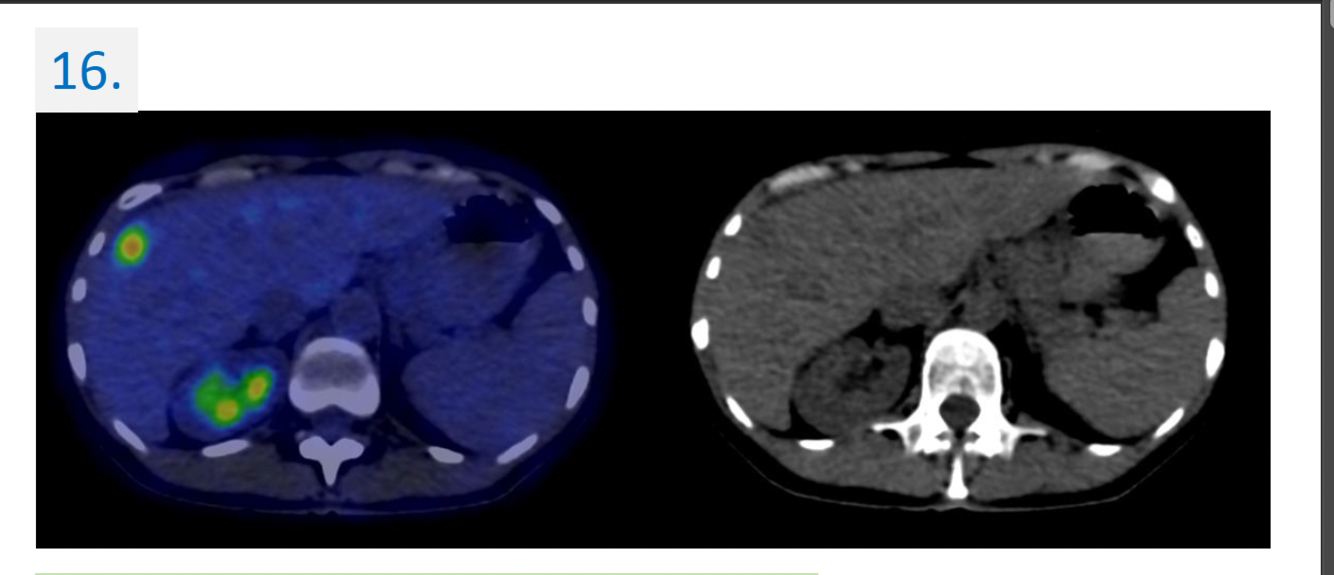

Modality:

FDG PET-CT (right panel: non-contrast CT) → 18(F)-fluoro-deoxy-glucose

Region:

upper abdomen, axial view

Diagnosis:

Malignant tumor → colorectal cc. metastasis → liver

16.